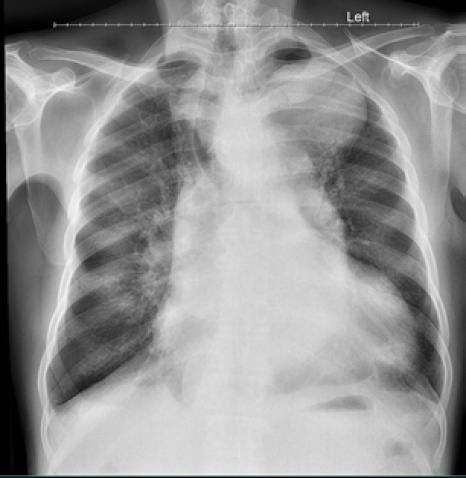

Method: This is a case report of a 58-year-old man with breathlessness and features of congestive cardiac failure. Preliminary chest X-ray revealed a huge soft tissue opacity in the left upper zone of the lung which was conformed as aneurysmal dilatation of the thoracic aorta on chest computed tomography.